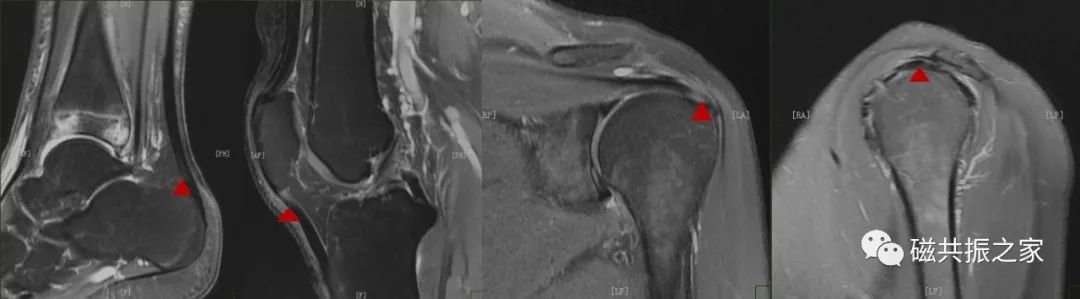

在临床扫描中经常会见到上图中的局部异常信号,对于这些异常信号考虑是退行性改变?撕裂?

在MRI成像中,如果肌腱和主磁场的夹角接近55°,则肌腱的局部会在T1WI和PDWI上显示为高信号,图△箭头,但其在长TE序列(如T2WI )上显示为正常。这种魔角效应的存在可能会与病理情况相混淆,引起对MRI信号的误解读。